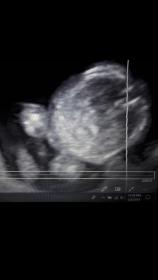

it's frontal photo from a video, 14+5,

This picture is not the type of shot good for guessing at this gestation.